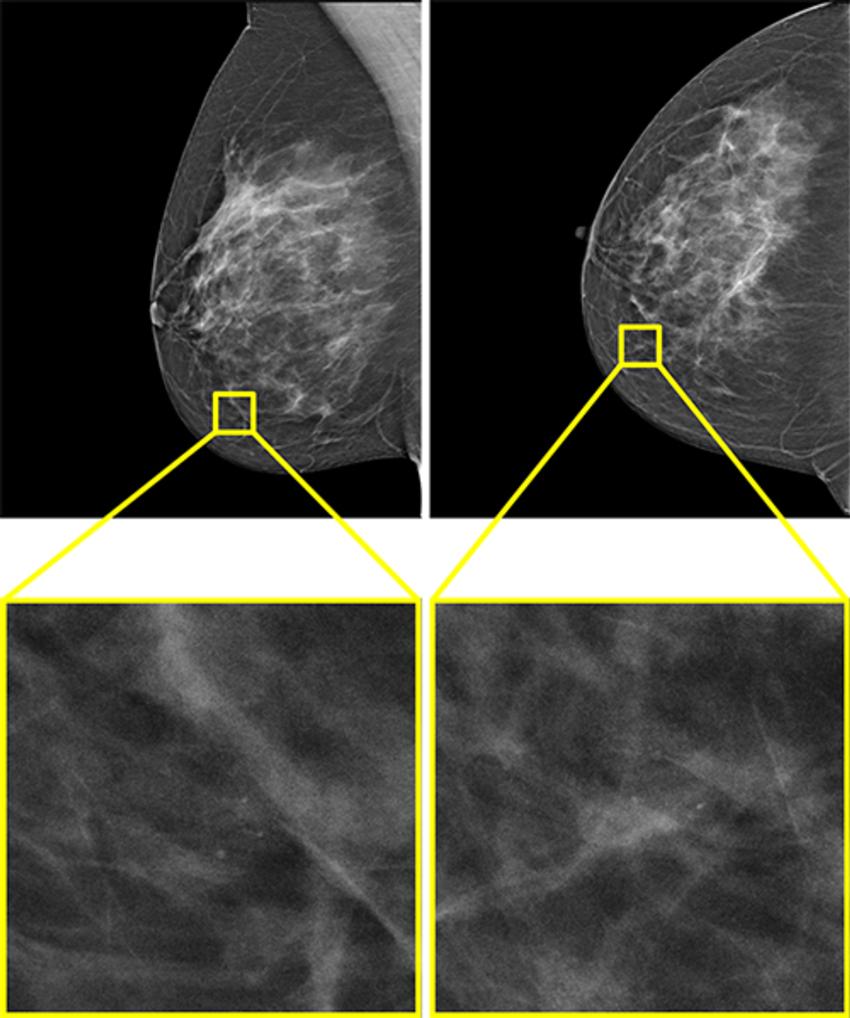

Figure 6. The only example of a screening examination with a screen-detected cancer that would have been missed by AI in a hybrid reading strategy based on the AI uncertainty score of the entropy of the mean probability of malignancy (PoM) score of the most suspicious region. During screening, a 52-year-old woman was recalled following arbitration scoring of the right breast as Breast Imaging Reporting and Data System (BI-RADS) 4 after the first and second radiologists scored the right breast as BI-RADS 1 and 4, respectively. This woman would not have been recalled if the examination was read by the AI model, which assigned a PoM score of 30, which would be classified as a certain prediction with an uncertainty quantification of 0.57. Both the mediolateral oblique (left) and craniocaudal (right) views of the affected breast are shown. The boxes indicate the calcifications found during screening, and the final diagnosis of this examination was ductal carcinoma in situ.